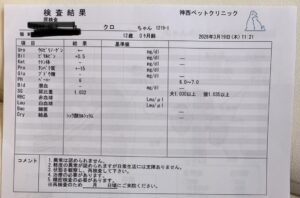

◾️キャットドックによる検査 診察

◾️診断

左の腎臓に石(腎結石)軽度の慢性腎臓病

甲状腺数値は正常高値→1〜2ヶ月後再検査

(甲状腺ホルモン薬が腎臓への負担となり逆効果となると危惧)

🍀半年後 血液検査 エコー